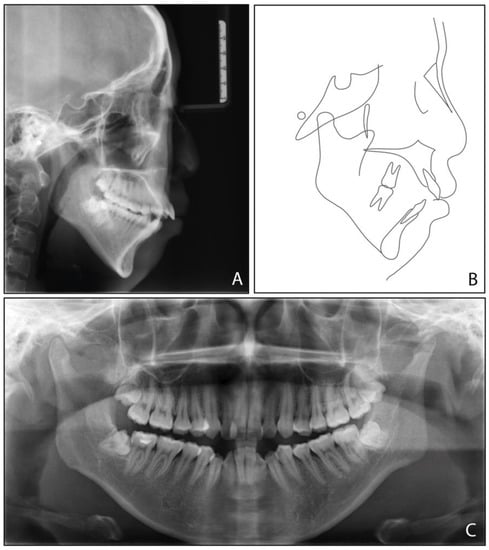

2.1. Diagnosis and Etiology

| Measurement | Normal Mean ± SD | Pretreatment | Posttreatment | Difference |

|---|---|---|---|---|

| SNA (°) | 83.1 ± 2.7 | 80.3 | 79.7 | −0.6 |

| SNB (°) | 80.3 ± 2.6 | 71.9 | 73.9 | 2 |

| ANB (°) | 2.7 ± 1.8 | 8.4 | 5.8 | −2.6 |

| UI-SN (°) | 103.4 ± 5.5 | 106.9 | 91.9 | −15 |

| LI-MP (°) | 96.3 ± 5.4 | 97.2 | 90.8 | −6.4 |

| UI-LI (°) | 129.1 ± 7.1 | 102.7 | 129.1 | 26.4 |

| MP-SN (°) | 32.6 ± 6.9 | 55.8 | 52.9 | −2.9 |

| MP-FH (°) | 25.5 ± 4.8 | 45.6 | 42.8 | −2.8 |

| Wits (mm) | −1 ± 1 | 5.8 | 2.8 | −3 |

| A-OP (°) | 10 ± 3.58 | 12.2 | 14.5 | 2.3 |

| P-OP (°) | 14.9 ± 3.85 | 25.1 | 16.2 | −8.9 |

| U1-PP (mm) | 28 ± 1.6 | 32.9 | 26.6 | −6.3 |

| U6-PP (mm) | 23 ± 1 | 24.4 | 19.3 | −5.1 |

| L1-MP (mm) | 40.8 ± 1.8 | 44.1 | 39.3 | −4.8 |

| L6-MP (mm) | 31.1 ± 1.9 | 33.4 | 28.9 | −4.5 |

| Palatal-OP (°) | 10 ± 4 | 17 | 15.7 | −1.3 |

| Upper Face Height (mm) | 50 ± 2.5 | 56.4 | 55.8 | −0.6 |

| Lower Face Height (mm) | 65 ± 4.5 | 81.1 | 75.4 | −5.7 |

| Anterior Face Height (mm) | 115 ± 5.5 | 135.9 | 130.8 | −5.1 |

| Posterior Face Height (mm) | 45 ± 5 | 75.9 | 73.2 | −2.7 |

| P-A Face Height (%) | 65 ± 4 | 55.8 | 56 | 0.2 |

| Y-Axis (°) | 67 ± 5.5 | 84.7° | 83.1 | −1.6 |

| UL-E (mm) | −1.6 ± 1.5 | 5 | −1 | −6 |

| LL-E (mm) | −0.2 ± 1.9 | 7 | −1.3 | −8.3 |